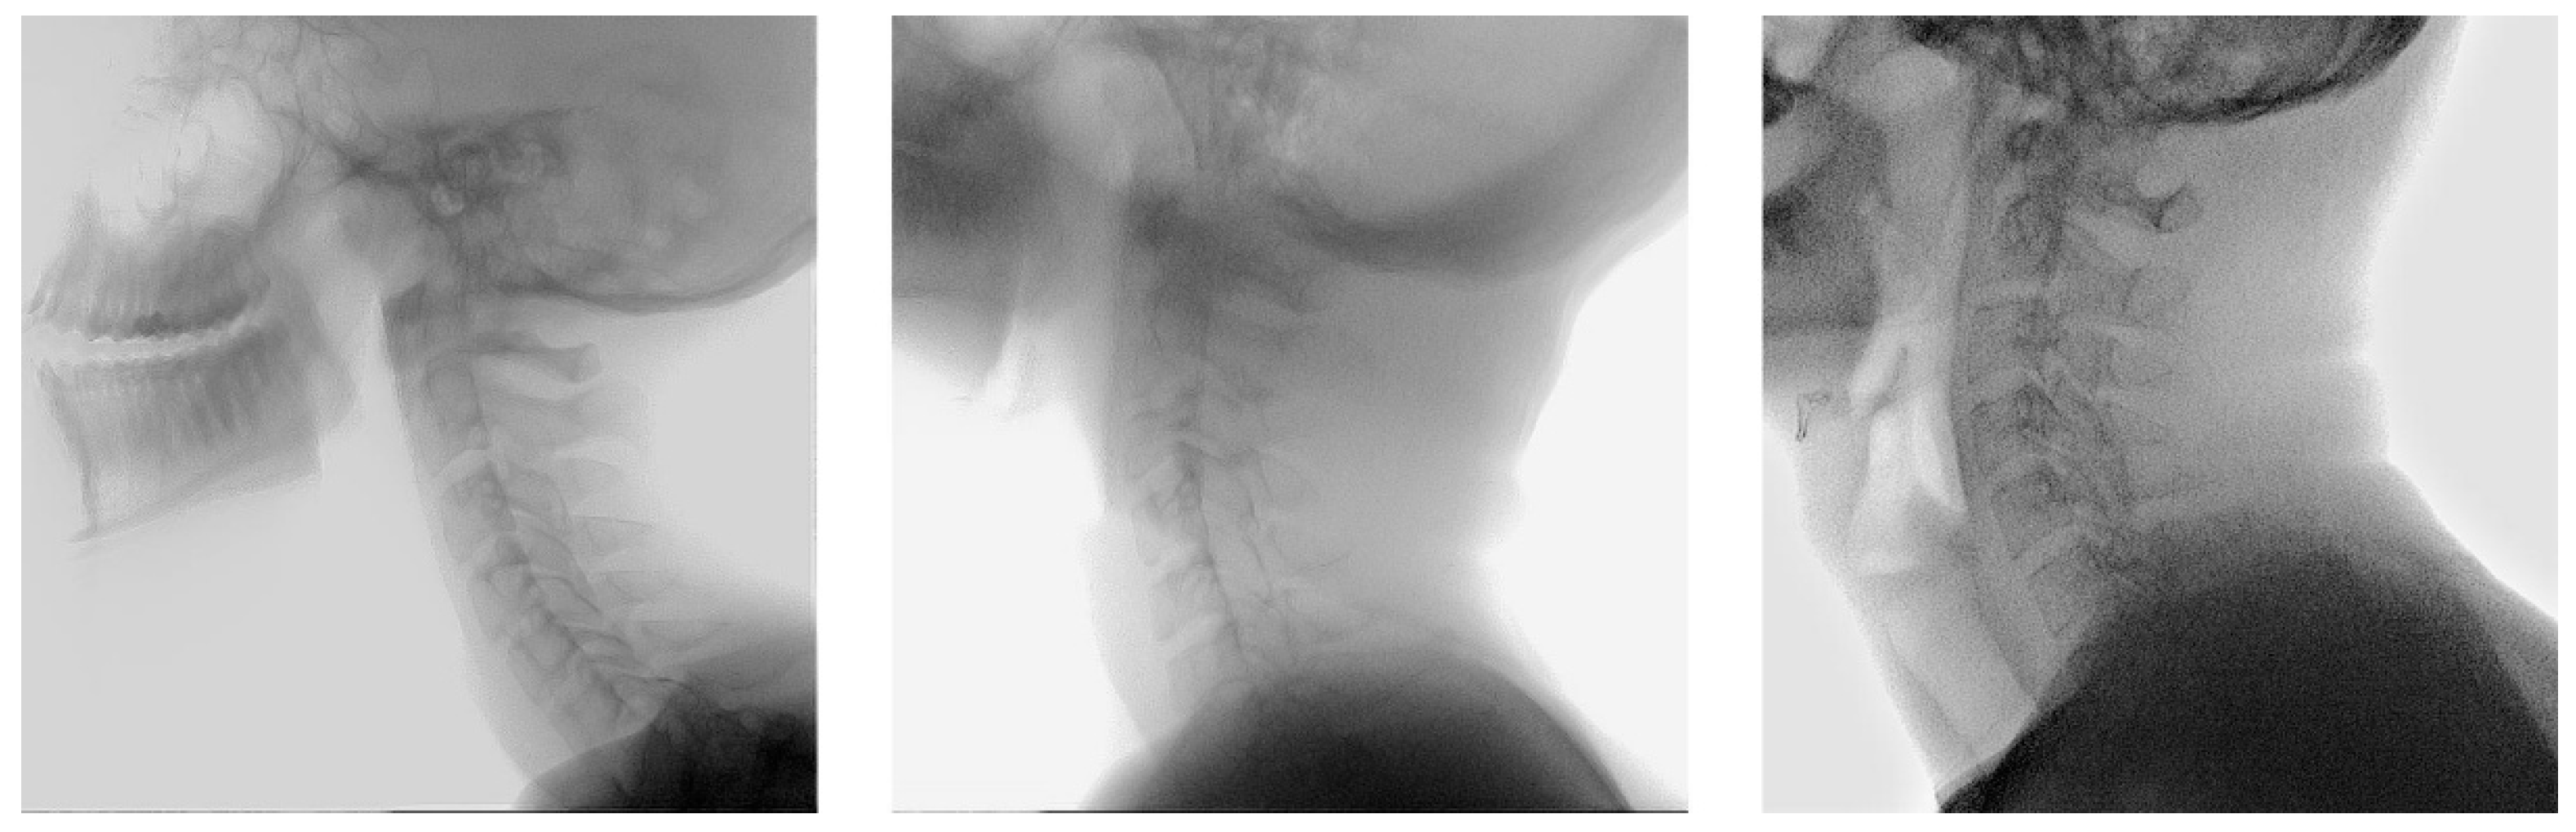

2.1. Population

2.2. Manual Annotation

2.3. Development of the Model

2.4. Dataset